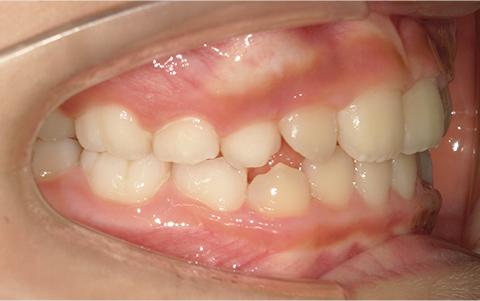

症例